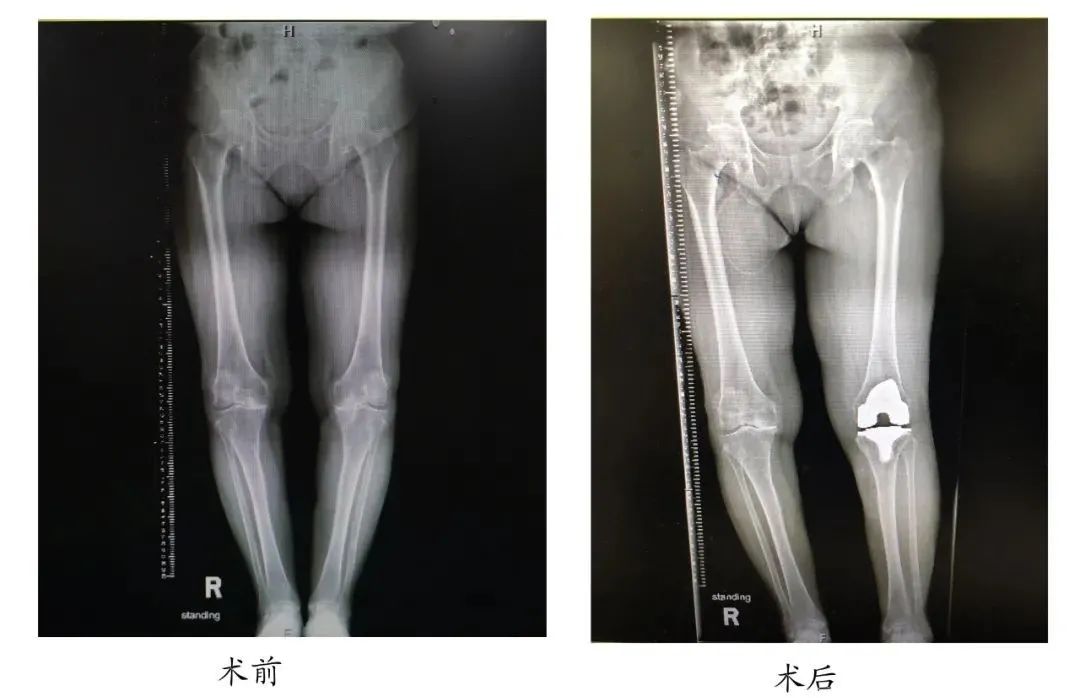

▲ 患者李女士术前X光片检查

66岁的李女士家住湖南衡阳,10年前双侧膝关节出现间断性刺痛,左侧较为严重,活动时疼痛加重,休息后可明显缓解。1年前,她双侧膝关节疼痛加重,并有明显的活动受限,上下楼略显吃力,下蹲略感困难。为进一步获得诊疗,她来到湘雅医院骨科门诊就诊,关节外科钟达副教授接诊了该患者。经检查发现,李女士双侧膝关节患有骨性关节炎,左侧膝关节较为严重并有畸形,左膝内侧半月板损伤Ⅲ级。

1月11日下午,钟达副教授为李女士实施了左侧全膝关节置换手术。术中实际使用假体型号与术前规划结果完全一致,术后力线恢复正常,患者对手术非常满意。

▲ 患者李女士术后X光片检查

▲ 患者李女士术前与术后的X光片检查